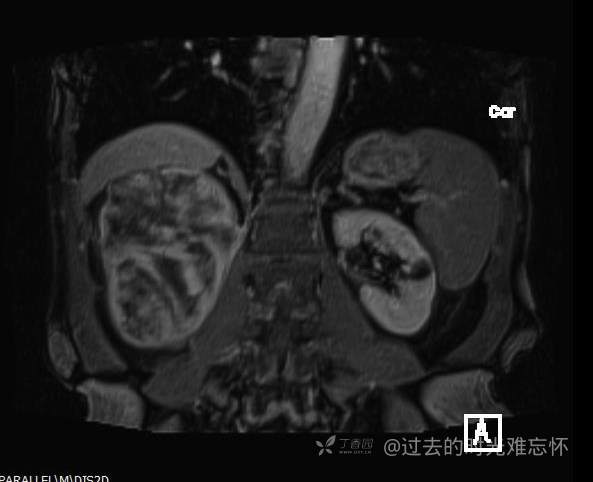

患者性别:男

患者年龄:73岁

主诉:咳嗽1月余。曾有血尿一次。后背部酸痛不适1-2年左右,无明显消瘦。

辅助检查:CT MRI

临床诊断:占位

治疗经过:手术

增强

黏液样脂肪肉瘤 (12)